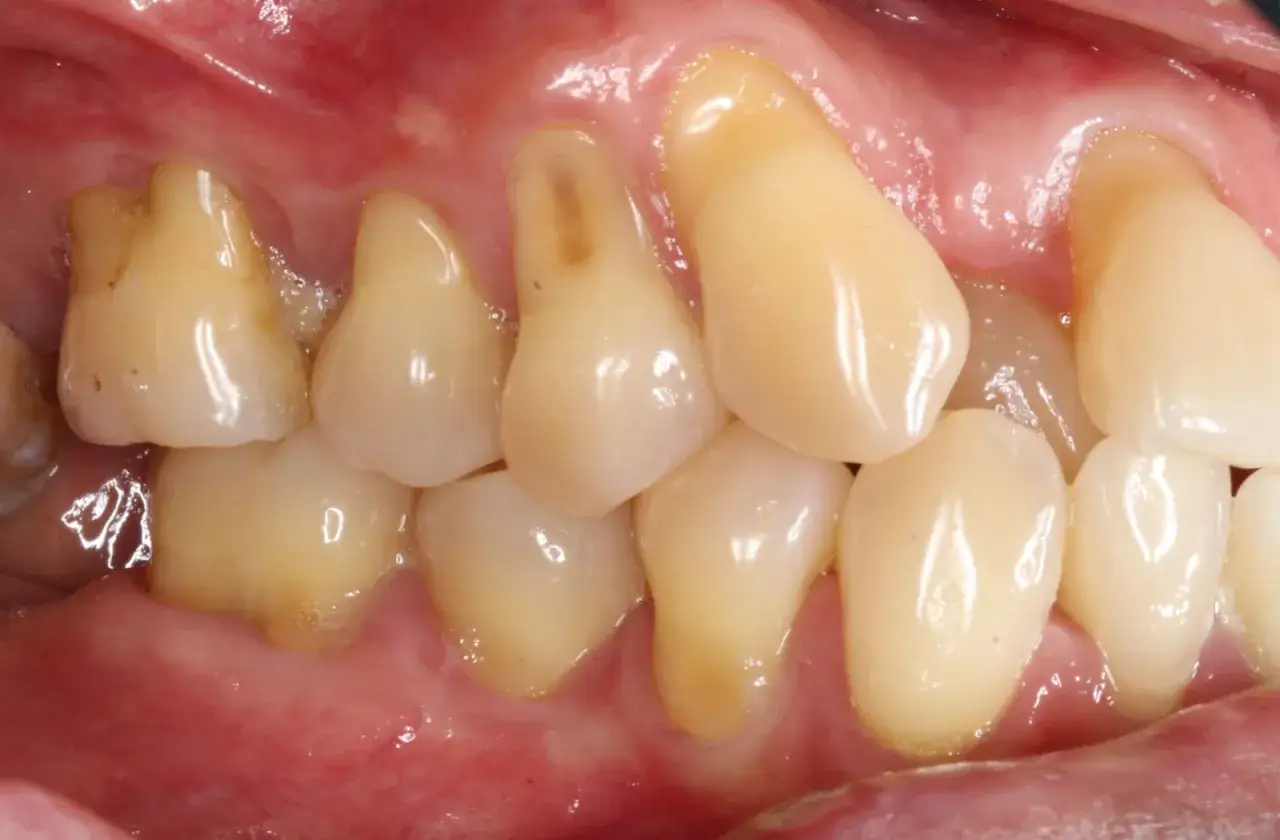

- Zmiana koloru zęba: Odsłonięty korzeń ma zazwyczaj ciemniejszy, żółtawy odcień w porównaniu do korony zęba, co może wpływać na estetykę uśmiechu.

Choroba przyzębia, znana również jako paradontoza (periodontitis), jest kluczowym czynnikiem prowadzącym do recesji dziąseł. To przewlekły stan zapalny, który dotyka tkanki otaczające ząb. Recesja często współwystępuje z periodontitis, czyli stanem zapalnym przyzębia, który może prowadzić do utraty kości i rozchwiania zębów. Mechanizm jest prosty: bakterie gromadzące się w płytce nazębnej i kamieniu wywołują stan zapalny. Organizm, próbując walczyć z infekcją, uruchamia procesy, które prowadzą do destrukcji kości wyrostka zębodołowego i włókien utrzymujących ząb w zębodole. W efekcie dziąsło, pozbawione podparcia, cofa się, odsłaniając korzeń. Według Merck Manual, periodontitis jest główną przyczyną utraty zębów u dorosłych i często towarzyszy jej recesja dziąseł.Cienki biotyp dziąseł, ustawienie zębów, wędzidełka i urazy mechaniczne

Istnieje szereg innych czynników, które mogą predysponować do rozwoju recesji dziąseł. Należy do nich cienki biotyp dziąseł – genetyczna predyspozycja do posiadania delikatnych, cienkich dziąseł, które są bardziej podatne na urazy i cofanie się. Nieprawidłowe ustawienie zębów w łuku, na przykład zęby wychylone poza łuk zębowy, mogą mieć cieńszą warstwę kości i dziąsła, co zwiększa ryzyko recesji. Obecność wysokich lub krótkich wędzidełek warg i języka również może przyczyniać się do cofania się dziąseł, ponieważ napinają one tkankę dziąsłową. Ponadto, inne urazy mechaniczne, takie jak piercing w jamie ustnej (np. w wardze lub języku), który ociera o dziąsła, a także nawykowe zaciskanie zębów (bruksizm) lub zgrzytanie nimi, mogą prowadzić do przeciążeń i w konsekwencji do recesji.

Recesja dziąseł natomiast to fizyczne cofnięcie się tkanki dziąsłowej, odsłaniające korzeń zęba. Może być ona konsekwencją długotrwałej paradontozy, gdzie utrata kości pociąga za sobą również cofanie się dziąsła. Jednak recesja może występować również niezależnie od aktywnego stanu zapalnego, na przykład w wyniku agresywnego szczotkowania, cienkiego biotypu dziąseł czy nieprawidłowego ustawienia zębów. Ważne jest, aby pamiętać, że choć te problemy często współistnieją, nie zawsze oznaczają to samo i wymagają różnego podejścia terapeutycznego.